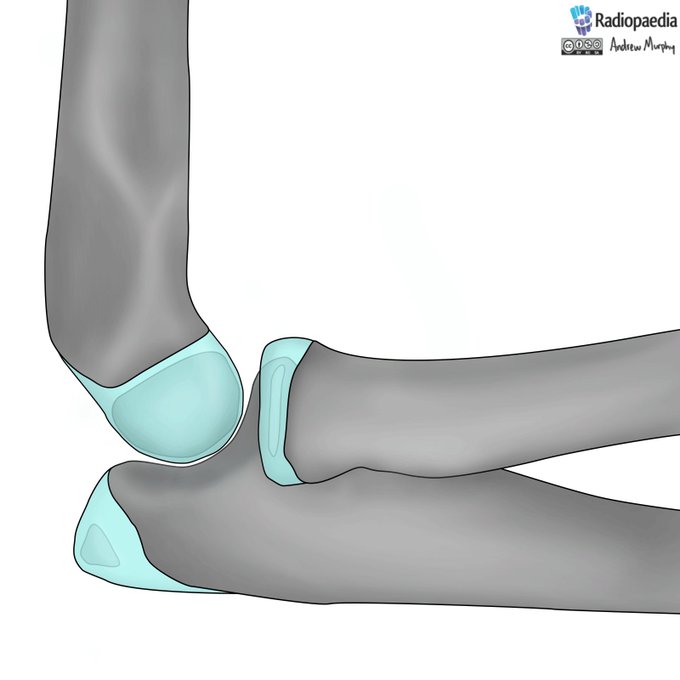

Small avulsion fractures of the knee are often a small part of the story. Missing them is not ideal

Here is a review guide I made as part of my knee image interpretation pathway.

Everything you kneed to know here: https://t.co/BgQpd2fGLJ